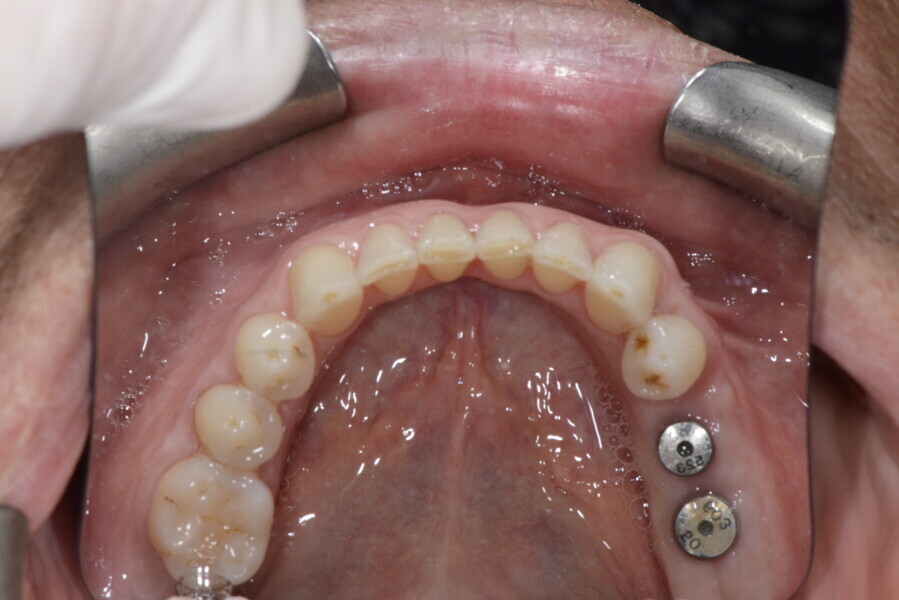

The 58-year-old patient wished to improve his oral aesthetics and function, complaining of mobility of the posterior teeth and wear of the anterior teeth. After data collection, a very complex situation was identified (Figs. 11–13):

1. severe periodontitis with poor prognosis of some teeth;

2. anterior crossbite;

3. severe wear mainly of the anterior teeth and compensatory eruption;38

4. atypical swallowing and lower posture of the tongue at rest;

5. masticatory dysfunction during the mastication test; and

6. no significant signs of temporomandibular disorder.

This patient, like all patients requiring interdisciplinary rehabilitation, had to first undergo periodontal treatment and caries restoration (Fig. 17). At the same time, it was important to rehabilitate swallowing with Froggymouth and relax the masticatory muscles and relieve the TMJs with an occlusal device. We could then study the orthodontic treatment plan using Invisalign ClinCheck (Align Technology) and showed the treatment plan to the interdisciplinary team and to the patient (Fig. 18). We were then able to create the correct sequence of orthodontic treatment, bone augmentation and implant surgery needed for the posterior edentulous spaces.

After the first phase of aligner treatment, we had achieved better inter-arch coherence, better maxillary arch expansion, and some space for improving the anterior tooth proportions restoratively (Fig. 19). We then temporarily restored the anterior teeth directly with composite, closing the spaces, improving the tooth proportions and further increasing the maxillary arch expansion (Fig. 20). We used restorative arch expansion to reduce the orthodontic destabilisation of the teeth to achieve the correct inter-arch coherence and retain the teeth in the cortical bone.38 A refinement aligner phase was undertaken to improve the final alignment of the gingival zenith and to improve the inter-arch coherence (Fig. 21). The periods of the first orthodontic phase and of the refinement were used to augment the mandibular and maxillary bone and to place the implants (Fig. 22). At the end of the orthodontic treatment, the case was finalised with ceramic veneers in the anterior area and temporary restorations on the implants in the posterior area (Figs. 23–26).